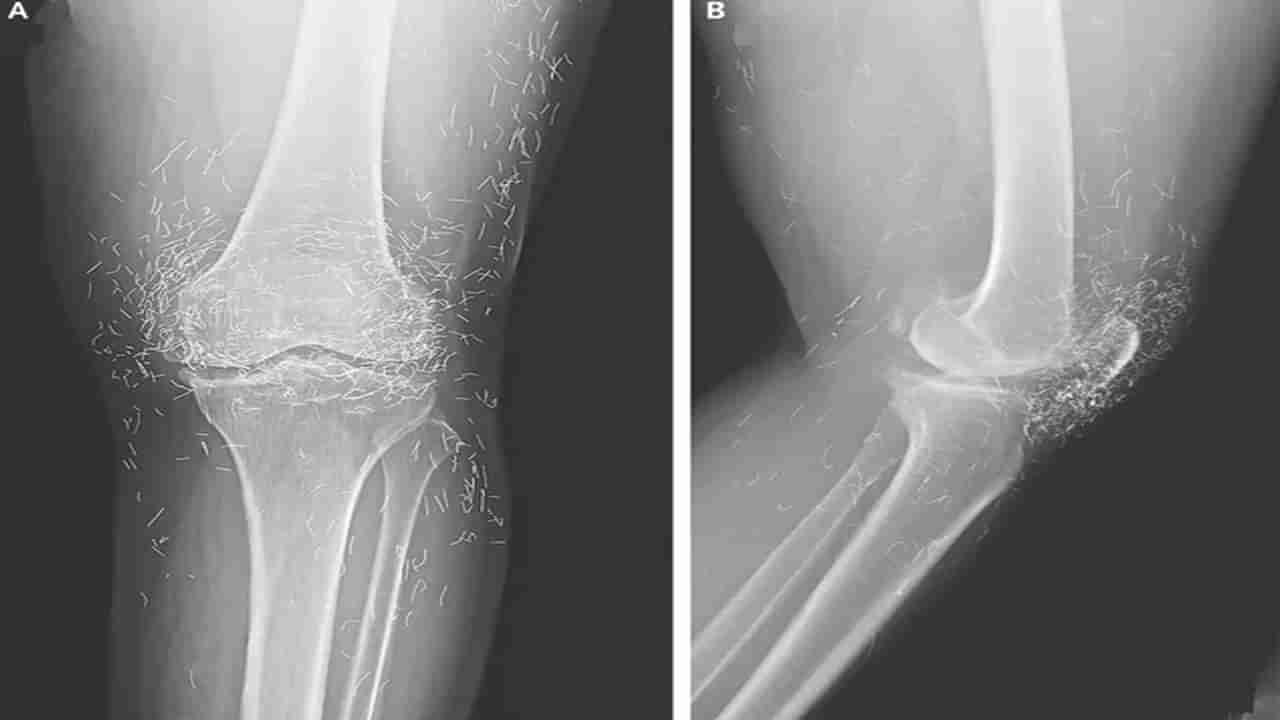

ఆ మహిళ తన కీళ్ల నొప్పులను తగ్గించుకోవడానికి వారానికి ఒకసారి ఆక్యుపంక్చర్ చేయించుకోవడం ప్రారంభించింది . నొప్పి చాలా తీవ్రంగా ఉన్నప్పుడు వారానికి అనేక సార్లు ఆక్యుపంక్చర్ చేయించుకోవడం మొదలు పెట్టింది. అయినా మోకాళ్లు నొప్పి భరించలేనిదిగా మారడంతో మళ్ళీ ఆసుపత్రిలో చేరింది. . వైద్యులు ఆ వృద్ధురాలి ఎడమ మోకాలికి ఎక్స్-రే తీశారు. ఎక్స్-రేలో కనిపించిన దృశ్యం చూసి షాక్ తిన్నారు. అందుకంటే మోకాలి చుట్టూ వందలాది చిన్న బంగారు తీగలు కనిపించాయి. ఈ తీగలు అసాధారణమైనవి కావని.. ‘గోల్డ్-థ్రెడ్ ఆక్యుపంక్చర్’ అనే ఒక చికిత్సా పద్ధతిలో భాగమని గుర్తించారు. అంతేకాదు మోకాలి కీలు లోపలి భాగంలోని షిన్బోన్ మందంగా గట్టిపడిందని చెప్పారు. మోకాలి కీలు దగ్గర షిన్బోన్ , తొడ ఎముక లోపలి భాగాలపై స్పర్స్ అని పిలువబడే ఎముక పెరుగ్తున్నట్లు గుర్తించారు.

ఆసియాలో ఆస్టియో ఆర్థరైటిస్ , రుమటాయిడ్ ఆర్థరైటిస్ రెండింటికీ చికిత్స చేయడానికి గోల్డ్-థ్రెడ్ అక్యుపంక్చర్ను సాధారణంగా ఉపయోగిస్తారని వైద్యులు చెప్పారు. అయితే, ఈ పద్ధతి పనిచేస్తుందని ఎటువంటి ఆధారాలు లేవు.. కొన్ని సందర్భాల్లో ప్రజలు సకాలంలో చికిత్స పొందకుండా నిరోధించడం ద్వారా పరోక్షంగా ఆర్థరైటిస్ను మరింత దిగజార్చుతుందని హెచ్చరిస్తున్నారు. ఈ బంగారు దారాలు శరీరం లోపలకు వెళ్లి.. శకలాలు పొరుగు కణజాలాన్ని దెబ్బతీస్తాయి. ఈ తీగలు శరీరంలోని ఇతర భాగాలలో చేరుకోవచ్చు.. దీనివల్ల తీవ్రమైన ఇన్ఫెక్షన్లు రావచ్చు హెచ్చరిస్తున్నారు.